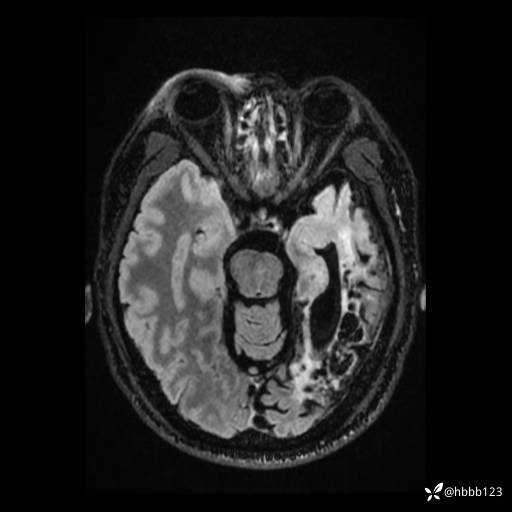

患者男,43岁。

简要病史:癫痫患者复诊,昨日发作5-6次,建议住院进一步治疗。

入院完善脑癫痫组合序列:

T2 Flair: